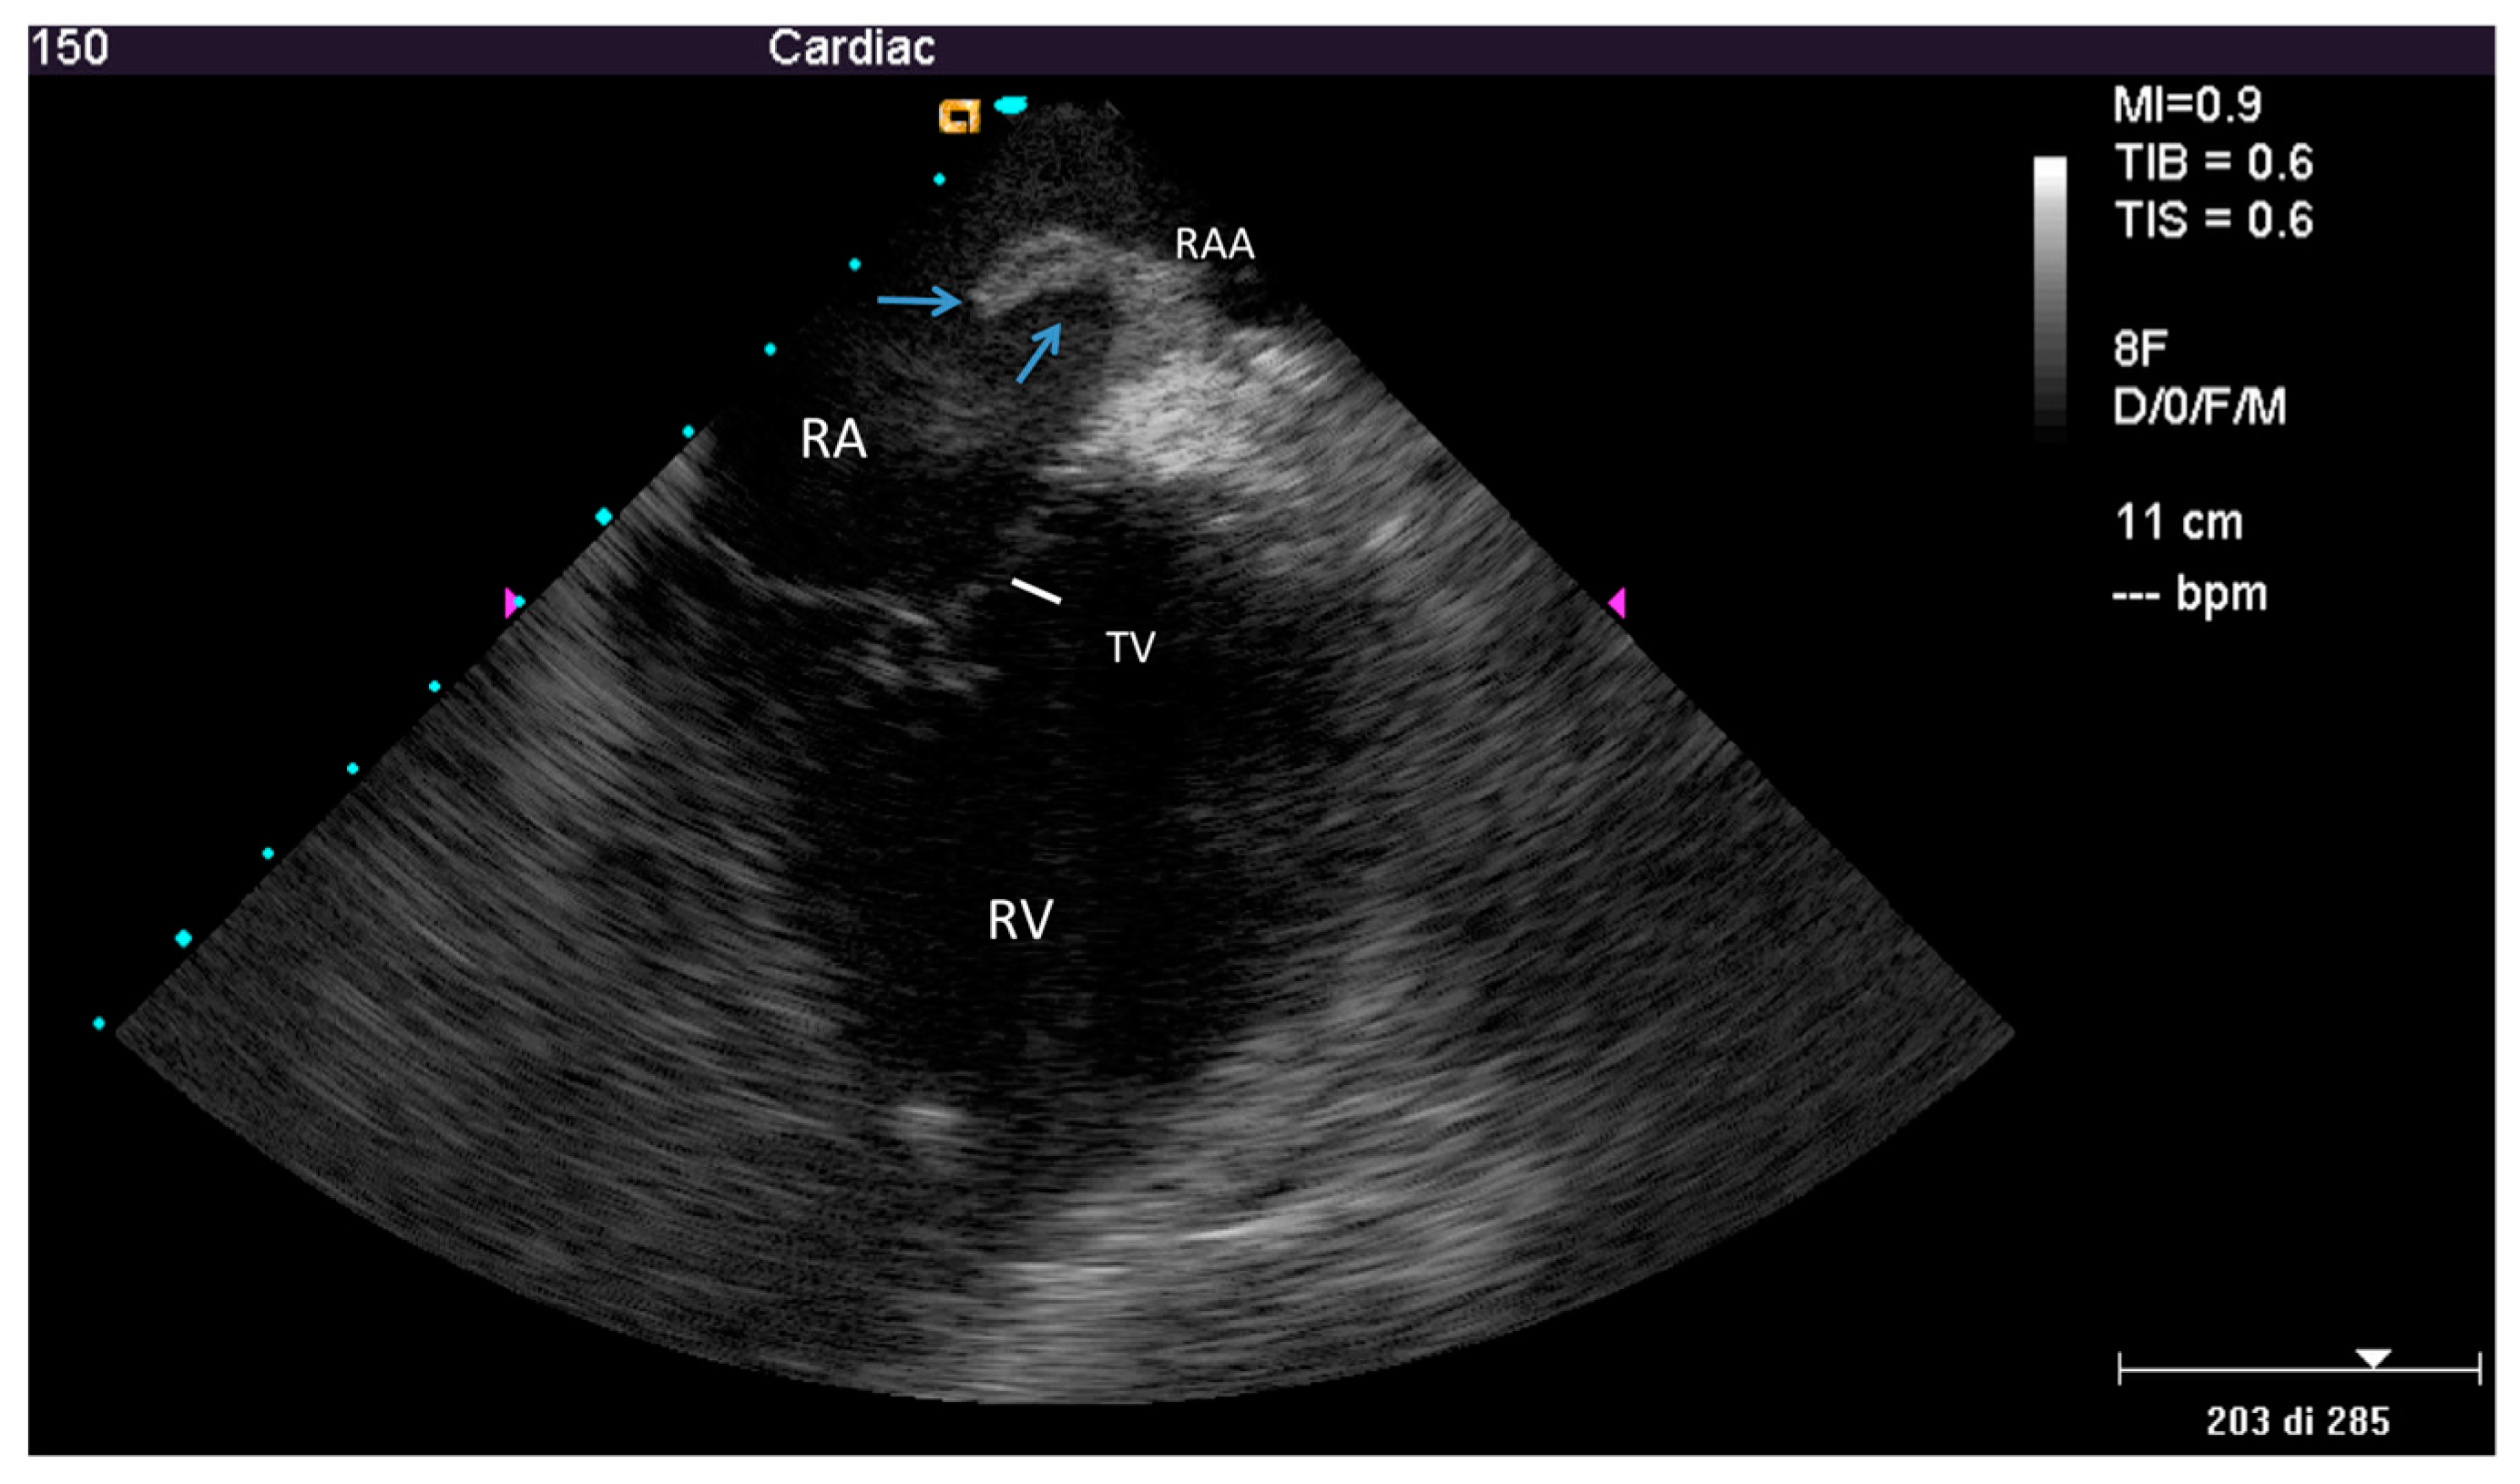

2.2.2. After the Extraction

3.2. Post-extraction ICE

4.2. Nature of the Ghost